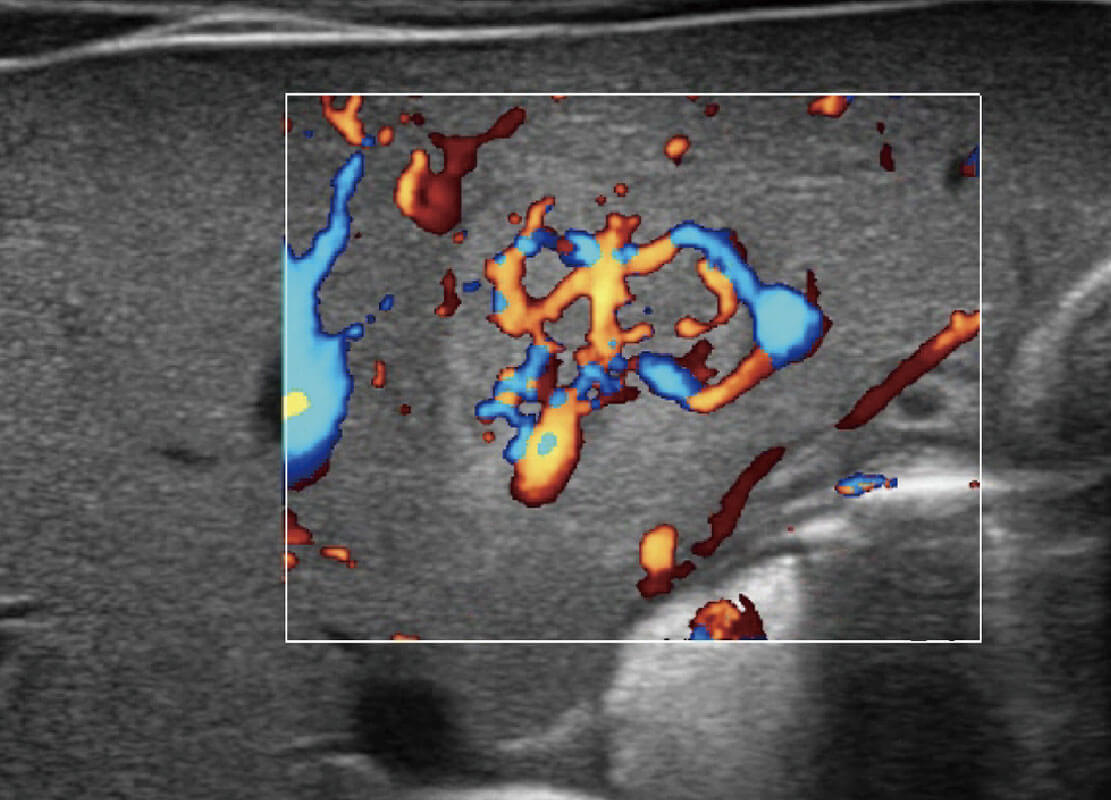

乳腺超声 / 新生儿

P60搭载宽频带线阵探头、宽景成像、弹性成像技术,为您提供乳腺应用方案。P60支持高频相控阵探头、线阵探头、腹部高频探头、腹部微凸探头等,丰富的探头群搭载敏感的彩色血流成像,适用于新生儿多种脏器检测要求,满足新生儿筛查需求。

• 新生儿肝血管癌